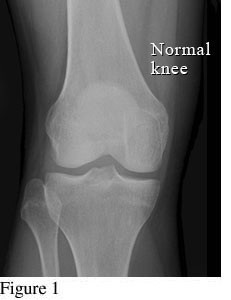

Hình ảnh so sánh giữa khớp bình thường và khớp bị thoái hóa khớp gối

Để phân biệt các giai đoạn của bệnh thoái hóa khớp gối, cần dựa vào phim X- quang theo tiêu chuẩn chẩn đoán thoái hoá khớp của Kellgren và Lawrence như sau:

Hình ảnh khớp gối trên phim X-quang: Khe khớp gần như bình thường, có thể có gai xương nhỏ.